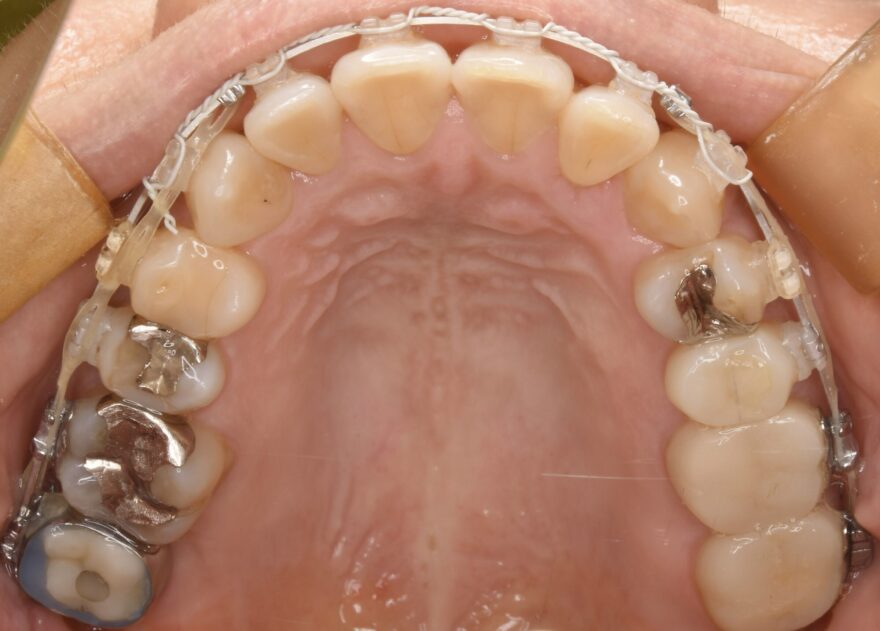

治療後の口腔内写真

なお前歯には、後戻り防止のためのワイヤーを装着しています。

下顎の前歯にも、後戻り防止のためのワイヤーを装着しています。